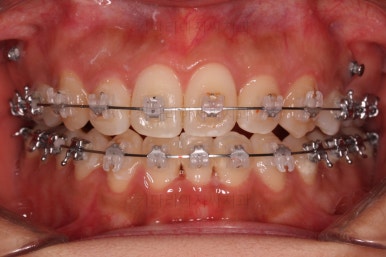

초진 시 입안의 모습입니다.

그냥 봐도 뭔가 애매함이 있죠?

중앙선이 맞지 않고, 교합이 떠보이는 양상이네요.

윗니는 좌측 작은 어금니가 한 개 모자랐고 아랫니는 앞니 하나가 모자라네요.

그런데 앞니는 아랫니가 1개 모자란 채로 교합이 맞춰져서 윗니가 하나 부족한 채로 애매한 상태였어요.